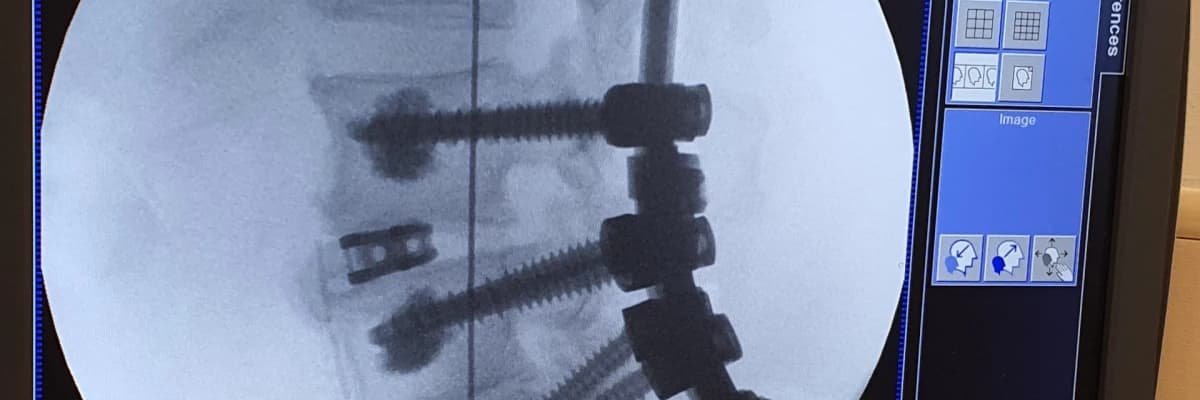

Vidalı omurga ameliyatı veya füzyon ameliyatında omurga cerrahı omurgalara vida koyar, bu vidaları birbirine rodlar yani metal çubuklar ile bağlar. Bu şekilde omurgalar hareketsiz kalır ve birbirine kaynar. Vidalı ameliyatın temel gerekçesi skolyoz gibi bel eğriliklerinde düzeltilen omurganın eski haline geri dönmesini engellemek, dar kanal gibi sinir sıkışması durumlarında ise yine hareketi kısıtlayarak sinir sıkışma ihtimali ortadan kaldırmak amaçlanır. Dar kanal ameliyatında vidalamanın diğer bir amacı sıkışan sinirleri rahatlatmak için kemikler alınabilir. Kemiklerin alınmasına bağlı olarak omurgada zayıflık oluşur, hem bu zayıflığı desteklemek hem de omurgaların birbiri üzerinde kaymasını engellemek için vidalı ameliyat gerekmektedir.

Spinal enstrümantasyon ise omurga vidalama işlemine denmektedir.

Vidalı omurga ameliyatında kullanılan vidalar, güncel olarak, titanyum, titanyum alaşımlı, paslanmaz çelik malzemesinden imal edilmiştir.

Türkiyede çok istisnalar dışın titanyum vidalar kullanılmaktadır. Vidaları birbirine bağlayan metal çubuklar (rod) da yine titanyum veya kobalt krom malzemeden imal edilmektedir. Bu malzemeler binlerce testten geçmiş ve uzun süredir kullanılan, insan biyolojisi ile uyumlu, insan vücudundan çıkarılması gerekmeyen malzemelerdir. Enfeksiyon veya vidalara bağlı rahatsızlık olursa platin dediğimiz vidalar ve rodlar çıkarılabilir.

Metal Çubuklar; metal rod olarak bilinirler. Metal rodlar omurgalara koyulan vidaları birbirine bağlamak için kullanılır.

Konektörler – ismindende anlaşılacağı gibi konnektörler rodları birbirine bağlar, bu şekilde aynı binanın çelik rekonstrüksiyonu gibi sağlam yapı elde eidlmiş olur.

Skolyoz ameliyatlarında, kifoz ameliyatlarında, dar kanal hastalığında, çoğu boyun fıtığı ameliyatında füzyon ameliyatı yapılır. Örneğin skolyoz ameliyatında vidalar omurgaya koyulur, eğrilik düzeltilir ve omurgaların birbirine kaynaması için (bu şekilde eğriliğin tekrar oluşması engellenir) vidalar birbirine metal çubuklar (rodlar) ile tutturulur. Hareketsiz kalan omurgada kemikler birbirine kaynadıktan sonra amacımıza ulaşmış oluruz. Bu işlemlerin hepsine Enstrümentasyon + Füzyon denmektedir.